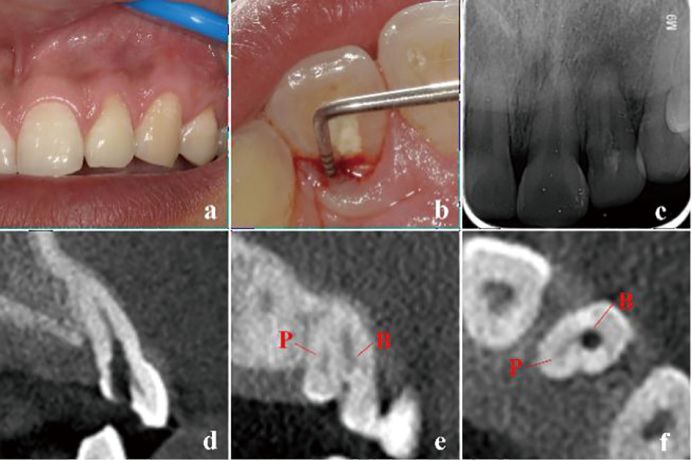

显微根管治疗结合意向性牙再植术治疗双根管上颌侧切牙畸形根面沟1例

Microscopic root canal therapy combined with intentional replantation for the treatment of palatogingival groove in the maxillary lateral incisor with two root canals: A case report

畸形根面沟(palatogingival groove,PGG)是一种位于根面的发育性解剖异常,多见于上颌侧切牙。PGG处牙周组织附着薄弱,易滞留菌斑,引起局部牙周炎症,感染可通过根面沟扩散至牙髓组织,最终导致牙周牙髓联合病变。本文报道了1例因畸形根面沟引起的左上颌侧切牙牙周牙髓联合病变,经显微根管治疗联合意向性牙再植术成功保留患牙,并进行文献回顾,探讨了PGG的诊断要点及治疗方案。

Palatogingival groove (PGG) is a developmental anatomical defect located on the lingual root surface, frequently observed in maxillary lateral incisors. The periodontal attachment in this region is delicate, which makes it vulnerable to plaque accumulation and increases the risk of periodontal inflammation, leading to combined periodontal-endodontic lesions. This article reports a case of a combined periodontal-endodontic lesion in a left maxillary lateral incisor caused by PGG. The tooth was successfully preserved through microscopic root canal therapy combined with intentional replantation. Additionally, a literature review was performed to highlight the key diagnostic features and treatment strategies for PGG.